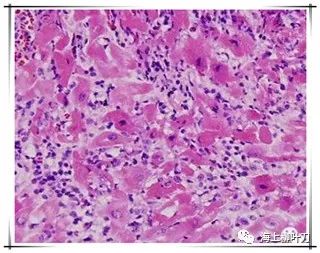

6.這是她的心肌病理切片,放大了100倍。

7.100倍還不是看得很清楚,放大400倍就很明顯了,一個(gè)個(gè)藍(lán)點(diǎn)就是淋巴球。這是很厲害的猛暴性心肌炎,整個(gè)心臟都被淋巴球浸潤(rùn)了。